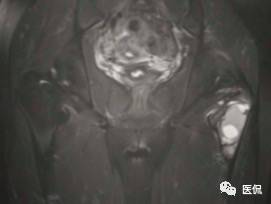

影像资料:

(3)MRI ABC的特征为鼓囊状的膨胀性破坏,呈单囊或由低信号的间隔分隔成大小不等的多囊。因血细胞和血浆的分离和沉淀,囊内可见液-液平面。在T2WI上,液面上层为高信号,下层为低信号;T1WI上则相反,上层为低信号,下层为偏高信号。液-液平面是ABC较特征的征象。增强检查低信号的纤维间隔呈环形强化。继发性动脉瘤样骨囊肿可在其原发病灶内有液-液平。

【诊断要点】发生于青少年长骨干骺端偏心膨胀的溶骨性病变,MRI检查病灶内见有液-液平征象时应首先考虑为动脉瘤样骨囊肿。